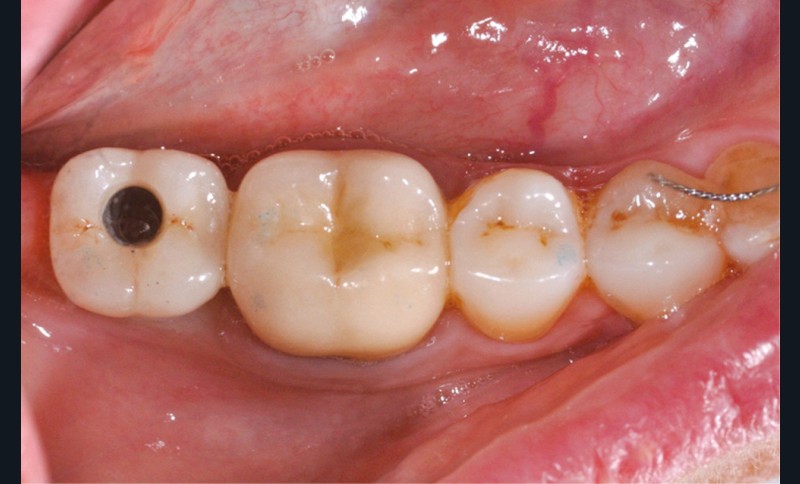

Le scellement de restaurations sur des piliers implantaires demeure une solution très intéressante (fig. 1). Cette technique reprend en effet les standards de la prothèse sur dent naturelle, à savoir un pilier implantaire (faux-moignon) vissé dans l’implant sur lequel est scellée une coiffe prothétique. Ses principaux atouts sont de corriger facilement les axes implantaires s’ils sont divergents par rapport à ceux des couronnes, tout en masquant l’émergence de la vis du pilier et conservant ainsi les faces occlusales intactes.

Il existe un risque (faible) de dévissage du pilier. La vis est alors enfouie sous la couronne collée et l’ensemble de la restauration bouge. Pour gérer cette complication, il est nécessaire de percer la face occlusale de la couronne pour la transformer en couronne transvissée. Elle pourra alors être replacée et vissée à l’aide d’une vis neuve. À ce titre, il est intéressant, au moins pour les cas où l’émergence implantaire n’est pas centrée sur la face occlusale, de faire une photographie archivée dans le dossier du patient pour savoir où chercher la tête de vis.

La seconde complication, plus grave, est le risque d’oublier des excès de ciment au niveau sous gingival. Ces derniers sont la cause principale avérée des péri-implantites et des pertes osseuses (fig. 2). Il est donc nécessaire de prendre toutes les précautions pour limiter au maximum ce risque.